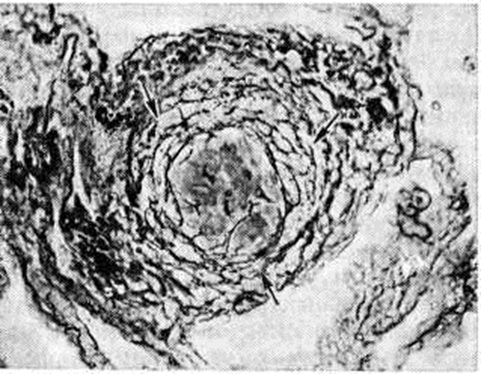

При силикозе и антракосиликозе в лёгких и регионарных лимфатических, узлах присутствуют типичные клеточнофиброзные и фиброзные узелки с концентрическим расположением коллагеновых и аргентофильных волокон (рисунок 1). Для силикатозов, особенно асбестоза, наряду с преобладанием интерстициального фиброза, захватывающего Межальвеолярные перегородки (фиброзирующий альвеолит), типично нахождение в лёгочной ткани особых телец (асбестовых, слюдяных и другие). Для антракоза характерно массивное скопление угольной пыли в лёгких, так называемый антракотические узелки, реже — узлы с пучкообразным расположением соединительнотканных волокон, с перибронхиальным и периваскулярным межуточным склерозированием и мелкоочаговой эмфиземой вокруг отдельных очажков. Количество угольной пыли в лёгких при антракозе может достигать значительных величин: у шахтёров, много лет проработавших под землёй, иногда обнаруживалось до 200 грамм угольной пыли в лёгких. При антракозе лёгкие могут быть окружены спайками чёрного цвета. Изменения в самой лёгочной ткани представляют собой сочетание краевой буллезной эмфиземы (смотри полный свод знаний Эмфизема лёгких) и диффузно-очагового пневмосклероза (смотри полный свод знаний). В очагах пневмосклероза определяются отложения пыли чёрного или серо-чёрного цвета. Бронхи расширены, встречаются бронхоэктазы (смотри полный свод знаний). Расстройство циркуляции крови и микроциркуляции в крупных очагах скопления пыли ведёт к дистрофическим и некротическим изменениям в лёгочной ткани с образованием антракотических каверн (смотри полный свод знаний Каверна). Развивается так называемый неспецифическая лёгочная чахотка (чёрная чахотка, phthisis atra). Узелки и узлы при антракозе могут сливаться друг с другом, занимая по площади долю лёгкого, чаще — нижнюю (опухолевидная форма антракоза). Регионарные лимфатических, узлы уплотнены, увеличены, чёрного цвета, реже поражаются шейные и забрюшинные лимфатических узлы. Скопления угольного пигмента иногда обнаруживаются в трахее, гортани, селезёнке, печени, почках. При микроскопическом исследовании эпителия трахеи и бронхов отмечают укорочение ресничек до их полного исчезновения и метаплазии эпителия в многослойный плоский. Атрофический, склерозирующий бронхит сопровождается нарушением выделительной функции мукоцилиарного тракта, что способствует большему накоплению пыли в лёгких. Более патогенная пыль антрацита вызывает выраженную реакцию «отграничения» и диффузный склероз лёгочной ткани. В антракотические узлы и регионарные лимфатических, узлы при антракозе часто происходит отложение извести. Истинный кальциноз лёгких при Пневмокониозы, при которых известь откладывается в склерозированных межальвеолярных перегородках и в фиброзных участках лёгочной ткани, следует отличать от кальциноза при нарушении функции паращитовидных желёз (смотри полный свод знаний Кальциноз) и от лёгочного альвеолярного микролитиаза. При вдыхании пыли металлического алюминия и содержащих его соединений и сплавов может развиться алюминоз, который приводит к выраженному склерозу лёгочной ткани и эмфиземе лёгких. Пневмосклероз при алюминозе поражает обычно верхние, доли обоих лёгких, которые, как правило, окружены спайками. Уплотнения в лёгких темно-серого цвета с серыми прослойками и тяжами, иногда виден характерный блестящий металлический оттенок (алюминиевые лёгкие). При алюминозе отмечают диффузный, преимущественно атрофический бронхит и эмфизему. Клиническая характеристика. Пневмокониозы, как правило, сопровождаются скудными клиническими проявлениями по сравнению с рентгенологически выявляемыми изменениями в лёгких. Симптоматика Пневмокониозы зависит от характера и степени дыхательной недостаточности, выраженности бронхита и эмфиземы, темпов прогрессирования пневмофиброза, аллергизации организма, наличия осложнений. Параллелизм между клинической картиной и рентгенологически определяемыми стадиями Пневмокониозы имеет место далеко не всегда. Характерно по мере прогрессирования фиброза постоянное нарастание симптомов дыхательной недостаточности (смотри полный свод знаний), однако у отдельных больных при наличии бронхита и эмфиземы лёгких одышка может быть значительной уже в I стадии болезни, тогда как у других выявляется лишь при физической нагрузке вплоть до III стадии. В начальных стадиях Пневмокониозы больных беспокоят главным образом сухой кашель, иногда спастического характера, одышка при тяжёлой физической работе, изредка — боли в груди. При объективном исследовании при наличии бронхита и эмфиземы можно обнаружить небольшое выбухание нижних отделов грудной клетки, при перкуссии — коробочный звук в нижнебоковых отделах грудной клетки. Аускультативно здесь определяется жёсткое, иногда несколько ослабленное везикулярное дыхание (смотри полный свод знаний). Без установки на выявление профзаболевания врач чаще всего диагностирует хронический бронхит (смотри полный свод знаний) и эмфизему лёгких (смотри полный свод знаний), которые обычно сопровождают Пневмокониозы По мере прогрессирования заболевания одышка возникает уже при небольшом физических напряжении, боли в груди становятся постоянными, кашель усиливается. Более выраженный характер принимает эмфизема или нарастает рестриктивная дыхательная недостаточность вследствие генерализации фиброза, снижается дыхательная экскурсия грудной клетки. Рассеянные сухие хрипы и очаги влажных мелкопузырчатых хрипов (смотри полный свод знаний) определяются в обоих лёгких на фоне жёсткого, ослабленного дыхания. В дальнейшем одышка приобретает характер ортопноэ, кашель становится мучительным, появляется мокрота, в которой иногда видны прожилки крови. Нередки приступы удушья. Перкуторно определяют притупление лёгочного звука над участками уплотнённой ткани лёгкого (плевральные сращения, очаги фиброза) и коробочный звук над остальными отделами лёгких. Часто выслушивается шум трения плевры. Все более выраженными становятся признаки лёгочной гипертензии с развитием лёгочного сердца (смотри полный свод знаний) и последующей его декомпенсацией, которая чаще всего служит непосредственной причиной смерти у больных Пневмокониозы Тяжесть Пневмокониозы связана также с осложнениями, из которых наибольшее значение имеет туберкулёз органов дыхания (смотри полный свод знаний). Антракоз и антракосиликоз нередко осложняются лёгочным кровотечением (смотри полный свод знаний) в связи с эрозией кровеносных сосудов, пролежнями антракотических узлов в стенке бронха с развитием лимфобронхиальных и пищеводно-бронхиальных свищей (смотри полный свод знаний Бронхиальный свищ), аспирационной пневмонией (смотри полный свод знаний), медиастинитом (смотри полный свод знаний) и даже гангреной лёгкого (смотри полный свод знаний). Диагноз. При установлении диагноза Пневмокониозы прежде всего необходимо учитывать так называемый профессиональный маршрут (вид производства, профессию, длительность работы, конкретные условия труда), санитарно-гигиенических характеристику производства с качественным и количественным анализом пыли и объективную симптоматику. Наибольшую информативность для постановки диагноза «пневмокониоз» имеют данные рентгенологического обследования (обзорная рентгенограмма лёгких, дополненная при необходимости боковым снимком, томограммами, рентгенограммами с прямым увеличением и так далее) в сочетании с общеклиническим обследованием больного. В последнее время все большее значение приобретает бронхофиброскопия (смотри полный свод знаний Бронхоскопия) с трансбронхиальной биопсией лёгочной ткани, позволяющая установить прижизненный морфологический диагноз заболевания. Обычно в комплекс методов исследования входит определение функции внешнего дыхания (смотри полный свод знаний). Функциональные нарушения не всегда соответствуют рентгеноморфологическим проявлениям Пневмокониозы В начале заболевания и при доброкачественном его течении функциональные нарушения чаще незначительны, преобладает лёгкая обструкция. При прогрессировании фиброза на обструкцию наслаивается рестриктивный синдром, при некоторых Пневмокониозы с картиной альвеолита развиваются диффузионные нарушения и возникает гипоксемия (смотри полный свод знаний Гипоксия). Картина крови при Пневмокониозы меняется мало. По мере прогрессирования заболевания может наблюдаться незначительная лимфопения на фоне умеренной лейкопении. При осложнениях возможен лейкоцитоз, моноцитоз, палочкоядерный сдвиг, ускорение РОЭ. При силикозе, асбестозе, бериллиозе часто наблюдают гипергаммаглобулинемию, очевидно за счёт увеличения количества иммуноглобулинов (смотри полный свод знаний). При тяжёлом течении Пневмокониозы, сопровождаемых осложнениями, часто отмечают увеличение содержания фибриногена, фракции α2-глобулинов, гаптоглобина, может быть обнаружен С-реактивный белок (смотри полный свод знаний), ревматоидный фактор (смотри полный свод знаний); коагуляционные пробы (смотри полный свод знаний) изменены: тимоловая и формоловая пробы — положительны, сулемовая проба по сравнению с нормой также изменена.